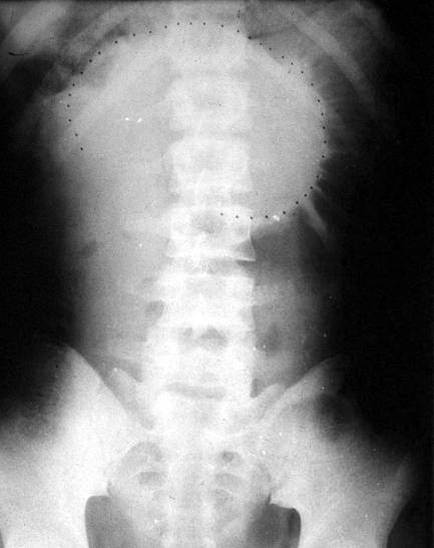

肠梗阻